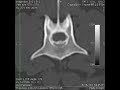

páteř / výhřez meziobratlové ploténky

Extruse disku na C5-C6 Lateralizovaný

výhřez disku (meziobratlové ploténky)